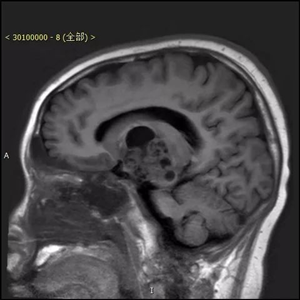

患者,男,入院时间2016年8月9日,入院时年龄13岁5月24天。主诉:右腿晃动3个月,伴右侧肢体力量减弱2个月。术后病理显示为囊性成熟型畸胎瘤,肿瘤组织内神经胶质细胞成分、平滑肌及腺上皮成分细胞异质性明显。

患者来到北京儿童医院就医时,由于肿瘤压迫脑功能区导致了瘫痪。北京儿童医院神经外科葛明教授及团队,对其进行了全切除手术,肿瘤直径4公分左右,手术路径深十公分左右,分块切除,历时四小时完整切除。术后患者瘫痪状态消失,随访恢复良好。

患者术前资料(下图)